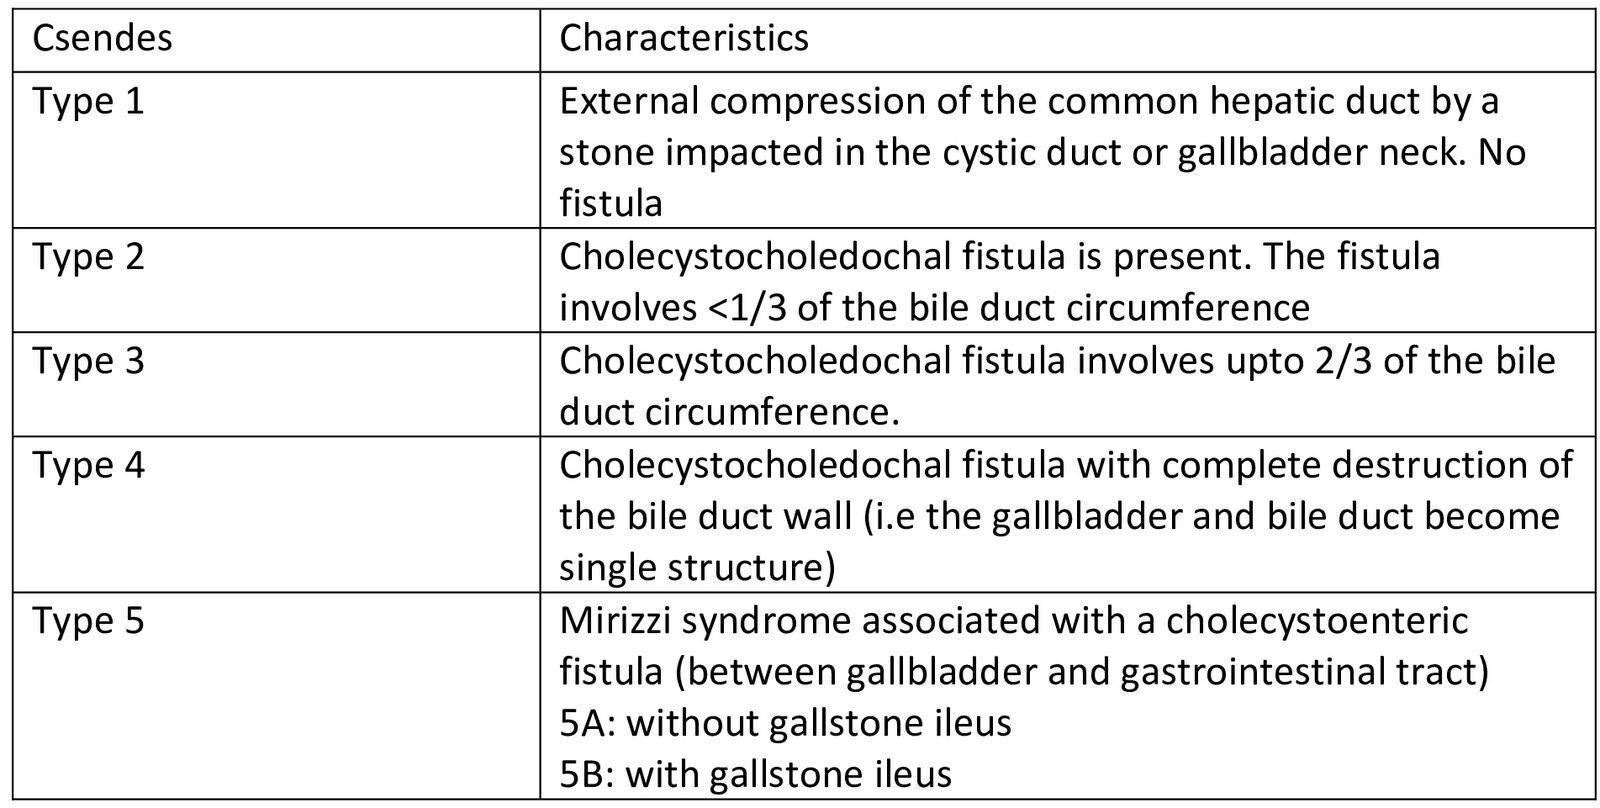

Mirizzi syndrome (MS) is an uncommon disorder brought on by external compression from impacted gallstones in Hartman’s pouch, which obstructs the common bile or common hepatic duct. While Hartman’s pouch is the commonest site of stone impaction, other known sites are the gallbladder neck and cystic duct.1 It is named after Pablo Luis Mirizzi, an Argentinean surgeon who first described it in 1940.1 It is an uncommon complication of chronic cholelithiasis. Mirizzi syndrome is uncommon, with an incidence generally less than 1% among patients with gallstone disease undergoing cholecystectomy, though rates may be higher in specialized centers or populations with longstanding or complicated gallstone disease.1,2 The Csendes classification is the most widely used system for categorizing MS. It describes five types based on the extent of common hepatic duct (CHD) or common bile duct (CBD) involvement by the impacted gallstone, as well as the presence and nature of a cholecystoenteric or cholecystobiliary fistula.2,3 An impacted gallstone causes a pressure ulcer, resulting in external compression of the main duct and eventually eroding into it. This inflammatory phenomenon describes the pathophysiological process leading to MS, at which point the disease may progress to a fistula, with varying degrees of contact between the bile duct and the gallbladder.4 MS poses considerable difficulties in diagnosis and management.

On examination, she was in fair general condition, afebrile and not icteric. The abdominal exam was normal. All relevant laboratory investigations were within normal ranges, and we proceeded with laparoscopic cholecystectomy. Intraoperatively, we noted extensive adhesions involving the gallbladder, omentum, and bowel. The gallbladder was firmly adherent to the cystic plate, rendering the surgery difficult. This prompted the team to opt for a bailout subtotal cholecystectomy. After dividing the gall bladder at the neck, a cholecystoduodenal fistula (Figure 3) less than 5mm was noted along with some bile leaks in the surgical field, reducing visibility. This led to the conversion to an open procedure through a midline incision. The duodenum was primarily repaired and secured with a pedicled omental flap. In an attempt to clearly define the biliary tree anatomy, we decided to explore the CBD. We made a 2cm incision on the anterior aspect of the CBD, which revealed a patent plastic stent in situ and multiple stones. The cystic duct was grossly dilated and found to be in continuity with the CBD. It contained multiple impacted stones, the largest measuring approximately 3cm. All stones were successfully extracted. A bile leak was noted at the cystic stump and was repaired primarily. The CHD was almost collapsed. The presence of a cholecystoenteric (cholecystoduodenal) fistula in a context of MS without gallstone ileus made us classify this as a Type 5A according to Csendes classification (Figure 4). The CBD was then repaired primarily. Abdominal irrigation was done, and a drain was left in situ. Postoperative monitoring was negative for bile leaks. The patient improved clinically, with liver function test normalising and was discharged after 10 days. Clinic follow-ups were scheduled every 3 months. The patient remained asymptomatic and is currently doing well and improving.